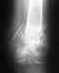

Для ответа на вопрос о допустимой нагрузке надо хотя бы увидеть, какой именно перелом бедра, и какой остеосинтез сделан, и как он сделан.